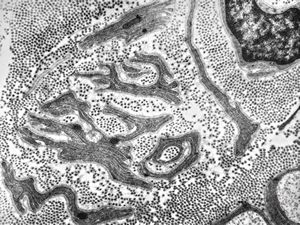

M,3y. | globoid leukodystrophy of Krabbe - n.suralis

M,3y. | globoid leukodystrophy of Krabbe - n.suralis

M,3y. | globoid leukodystrophy of Krabbe - n.suralis

M,3y. | globoid leukodystrophy of Krabbe - n.suralis

M,3y. | globoid leukodystrophy of Krabbe - n.suralis